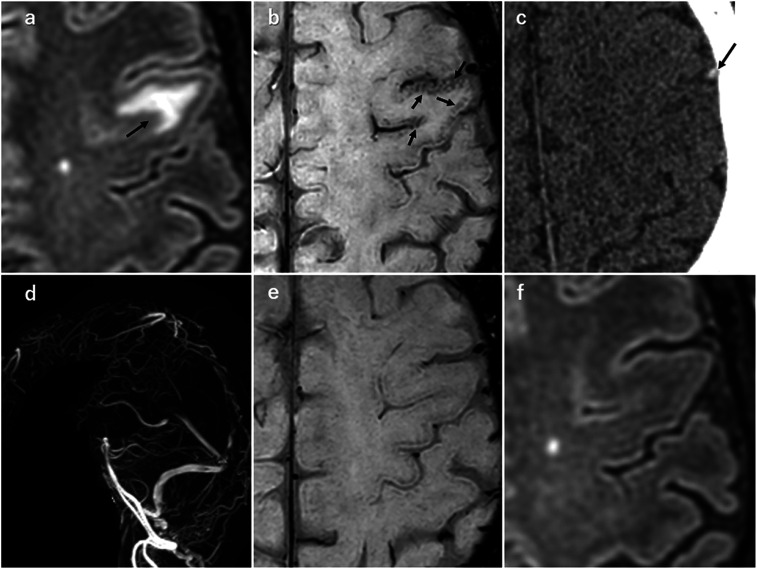

我们观察到一种新的 SWI 发现--"皮质刷状征",它代表了急性脑梗塞患者皮质中突出的静脉结构,无论患者是否患有莫亚莫亚病和脑静脉血栓形成。所有病例的皮质刷状征均在后续的 SWI 检查中消失。皮质刷状征有助于了解急性期皮质静脉结构的病理生理学。

We observed a new SWI finding, "cortical brush sign," that represents prominent venous structures in the cortex of patients with acute cerebral infarct with or without moyamoya disease and cerebral venous thrombosis. The cortical brush sign disappeared on follow-up SWI in all cases. Cortical brush sign may help to understand the pathophysiology of venous structures in the cortex at acute phase.